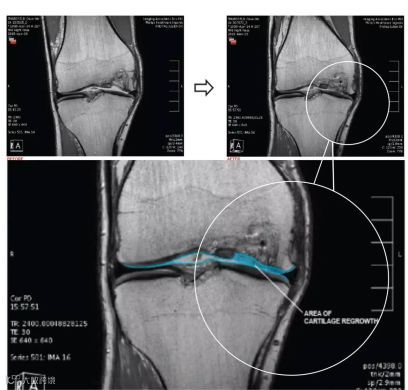

《Herald Sun》报道,澳大利亚医学家用干细胞再生受损的膝盖软骨,这项研究是与麦哲伦干细胞(Magellan Stem Cells)合作完成,由莫纳什大学和拉筹伯大学监督,是澳大利亚首例试验,将患者自身的分离和扩展的间充质干细胞注入到自己的膝关节中,两项研究共涉及70名患者。

最初的结果显示,那些在墨尔本干细胞治疗中心(Melbourne Stem Cell Centre)的病人中,有一半病人感受到的痛苦减少了四分之三,并且膝关节功能有了很大的改善。部分患者的关节再生,尤其是当MRI图像显示26岁的患者Ollie Thursfield的膝盖十年之久的缝隙居然被新的软骨填补。